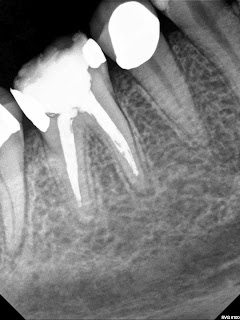

Mid mesial canal and a ribbon shaped canal in MB canal almost 4 canals. Depending on how you shaped this it would be considered 3 or 4 canals. Appears that mid mesial joins ML.

| CaOH |